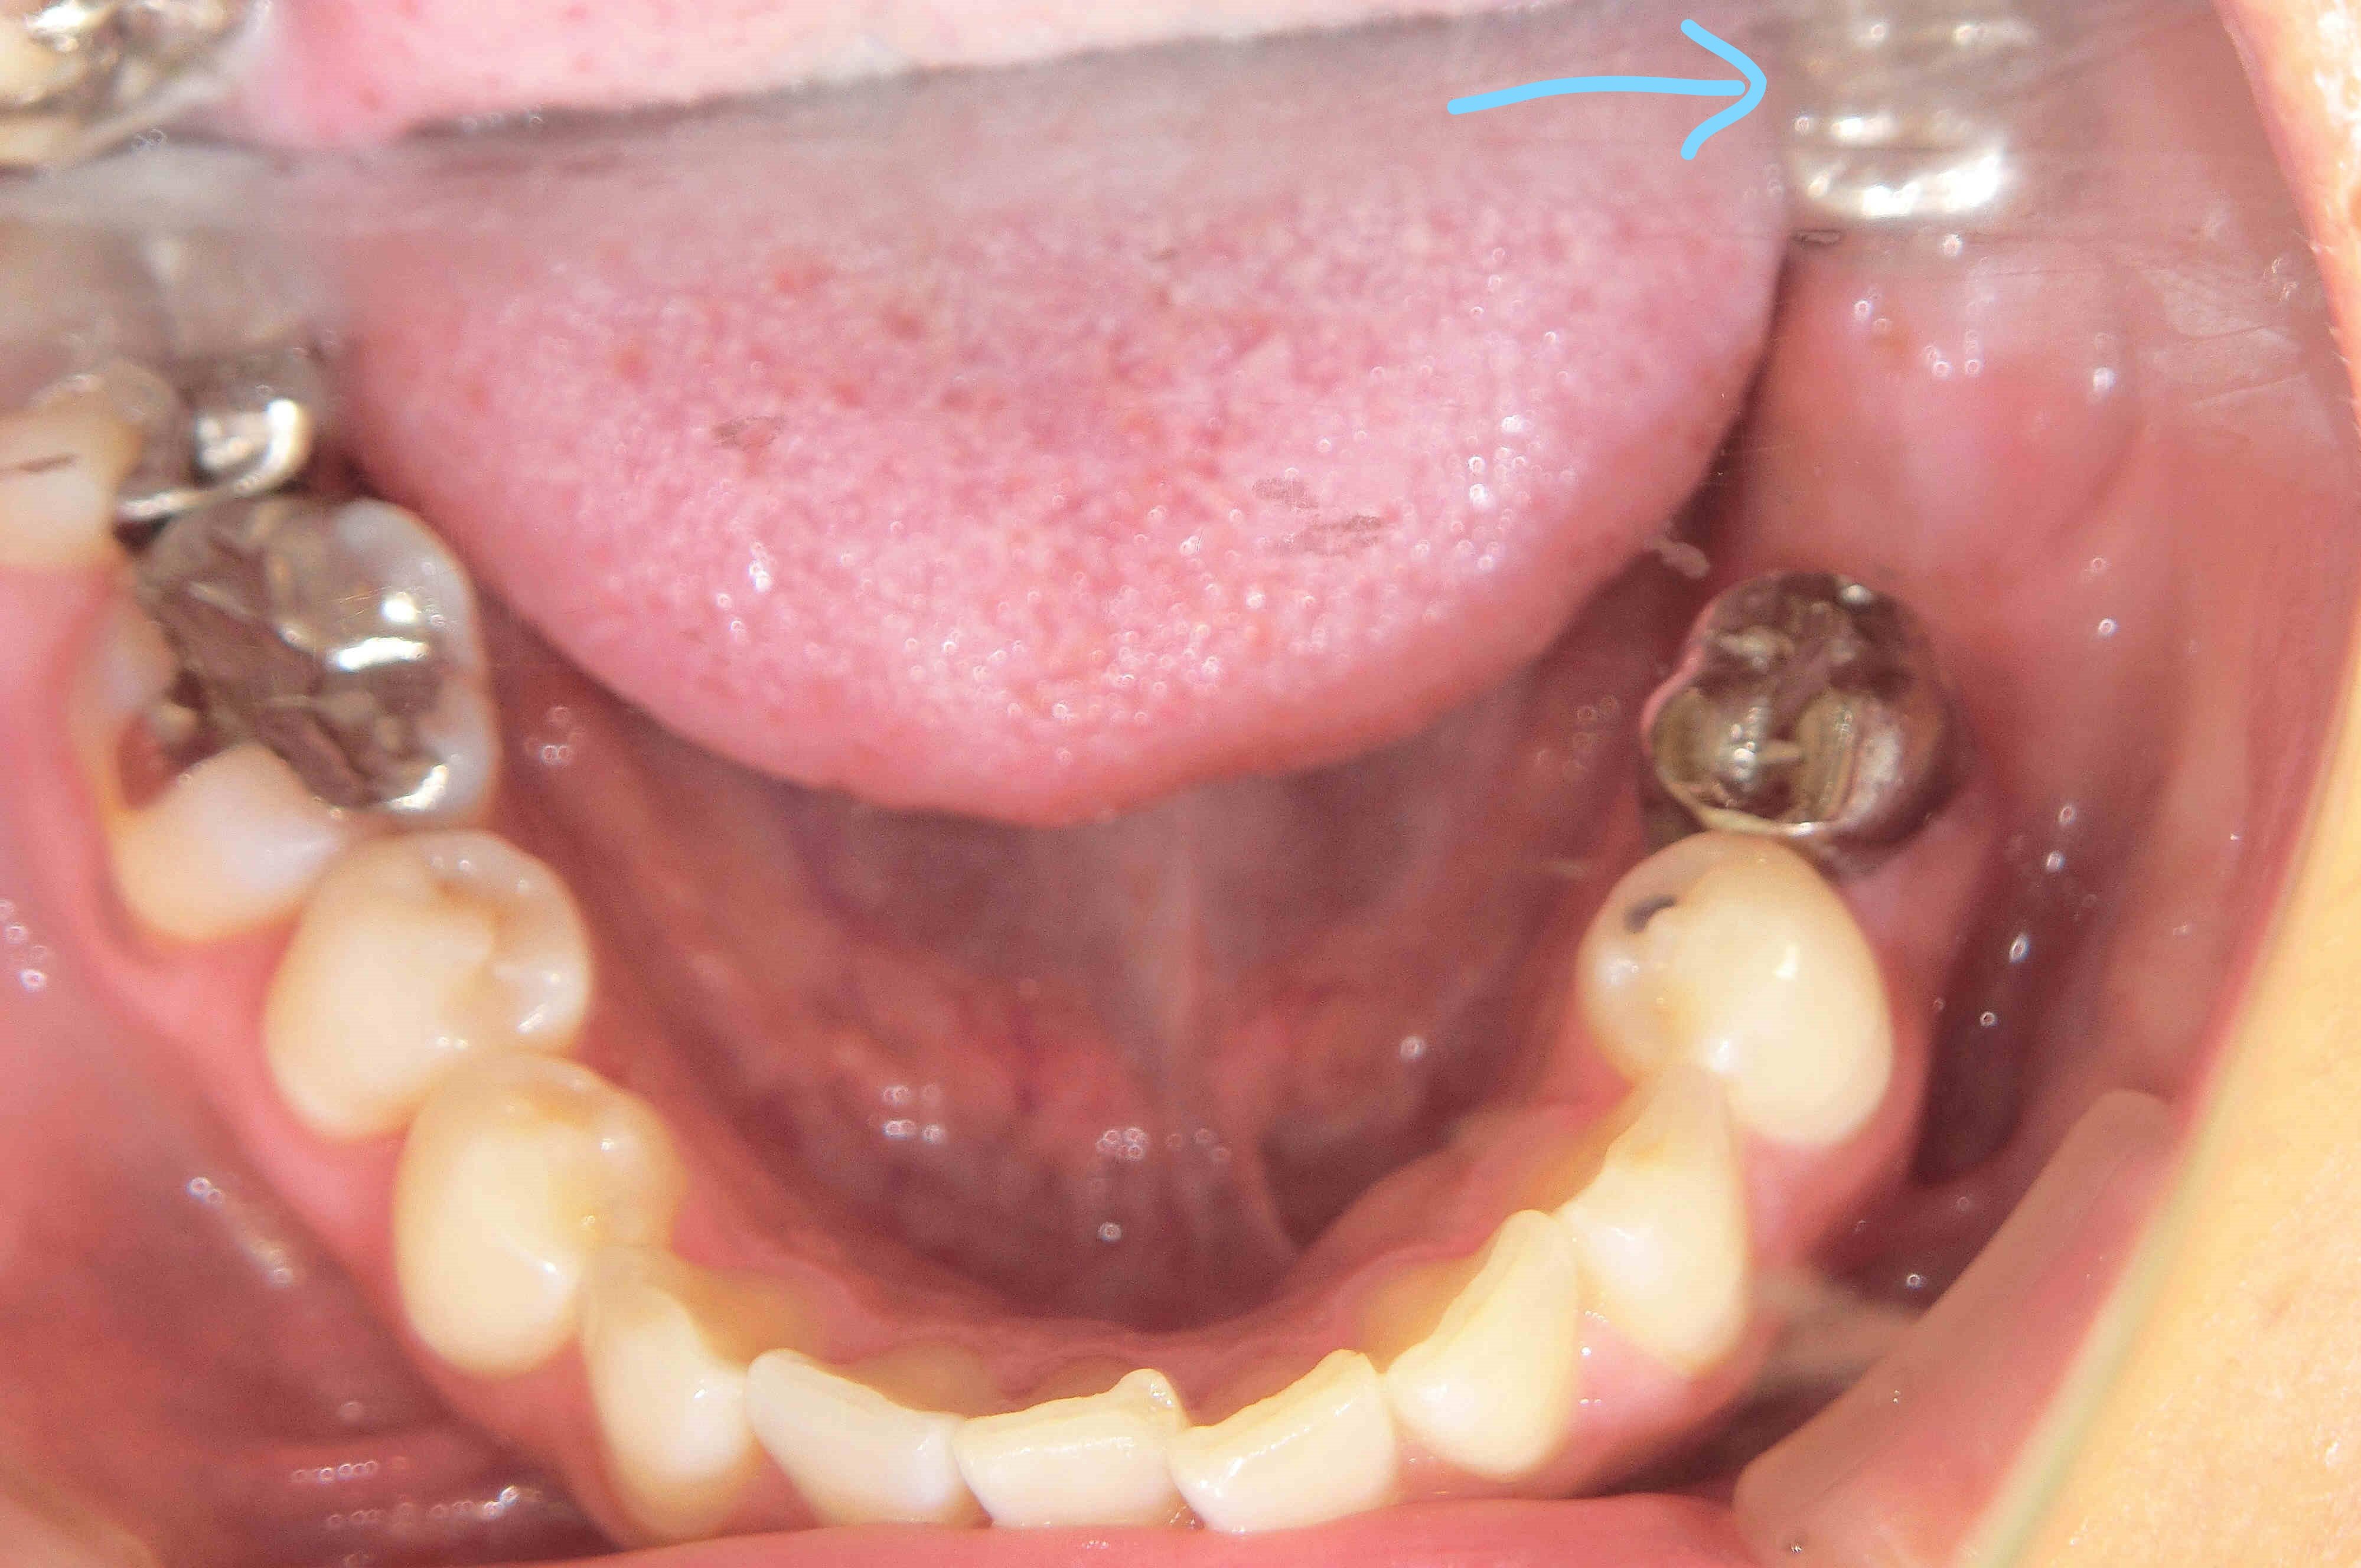

その後、患者さまは「隣接歯に負担のかかるブリッジや入れ歯ではなく、インプラントによる治療を希望」され、左下奥歯部にインプラントとセラミック冠(メタルボンド)を用いた治療を実施しました(右下の写真参照/水色矢印部)。

メタルボンド冠は、セラミック製の外装を持ち、歯垢(プラーク)が付着しにくい構造となっており、インプラント周囲炎などのリスク軽減にも配慮されています(※個人差があります)。